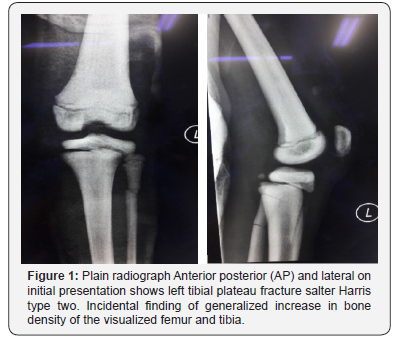

Ms A, an eight- year old girl met in a road traffic accident (motorcycle versus car). She was the pillion rider on a motorcycle rode by her sister. While making a U-turn, the front of their motorcycle was hit by a car at the speed of 30-40kmPH causing them to lose control of the motorcycle and she fell sideways landing on her left knee. There was no direct impact to her. She presented to the emergency department with complain of left knee pain, swelling and inability to weight bare. She was diagnosed with closed left tibial plateau fracture salter Harris type two and proximal third fibula fracture (Figure 1). She underwent closed reduction and percutaneous K-wiring of her left proximal tibia (Figure 2) which subsequently was complicated with osteomyelitis (Figure 3). On retrospective review of her initial plain radiograph, it was noticed to show generalized increase in bone density.